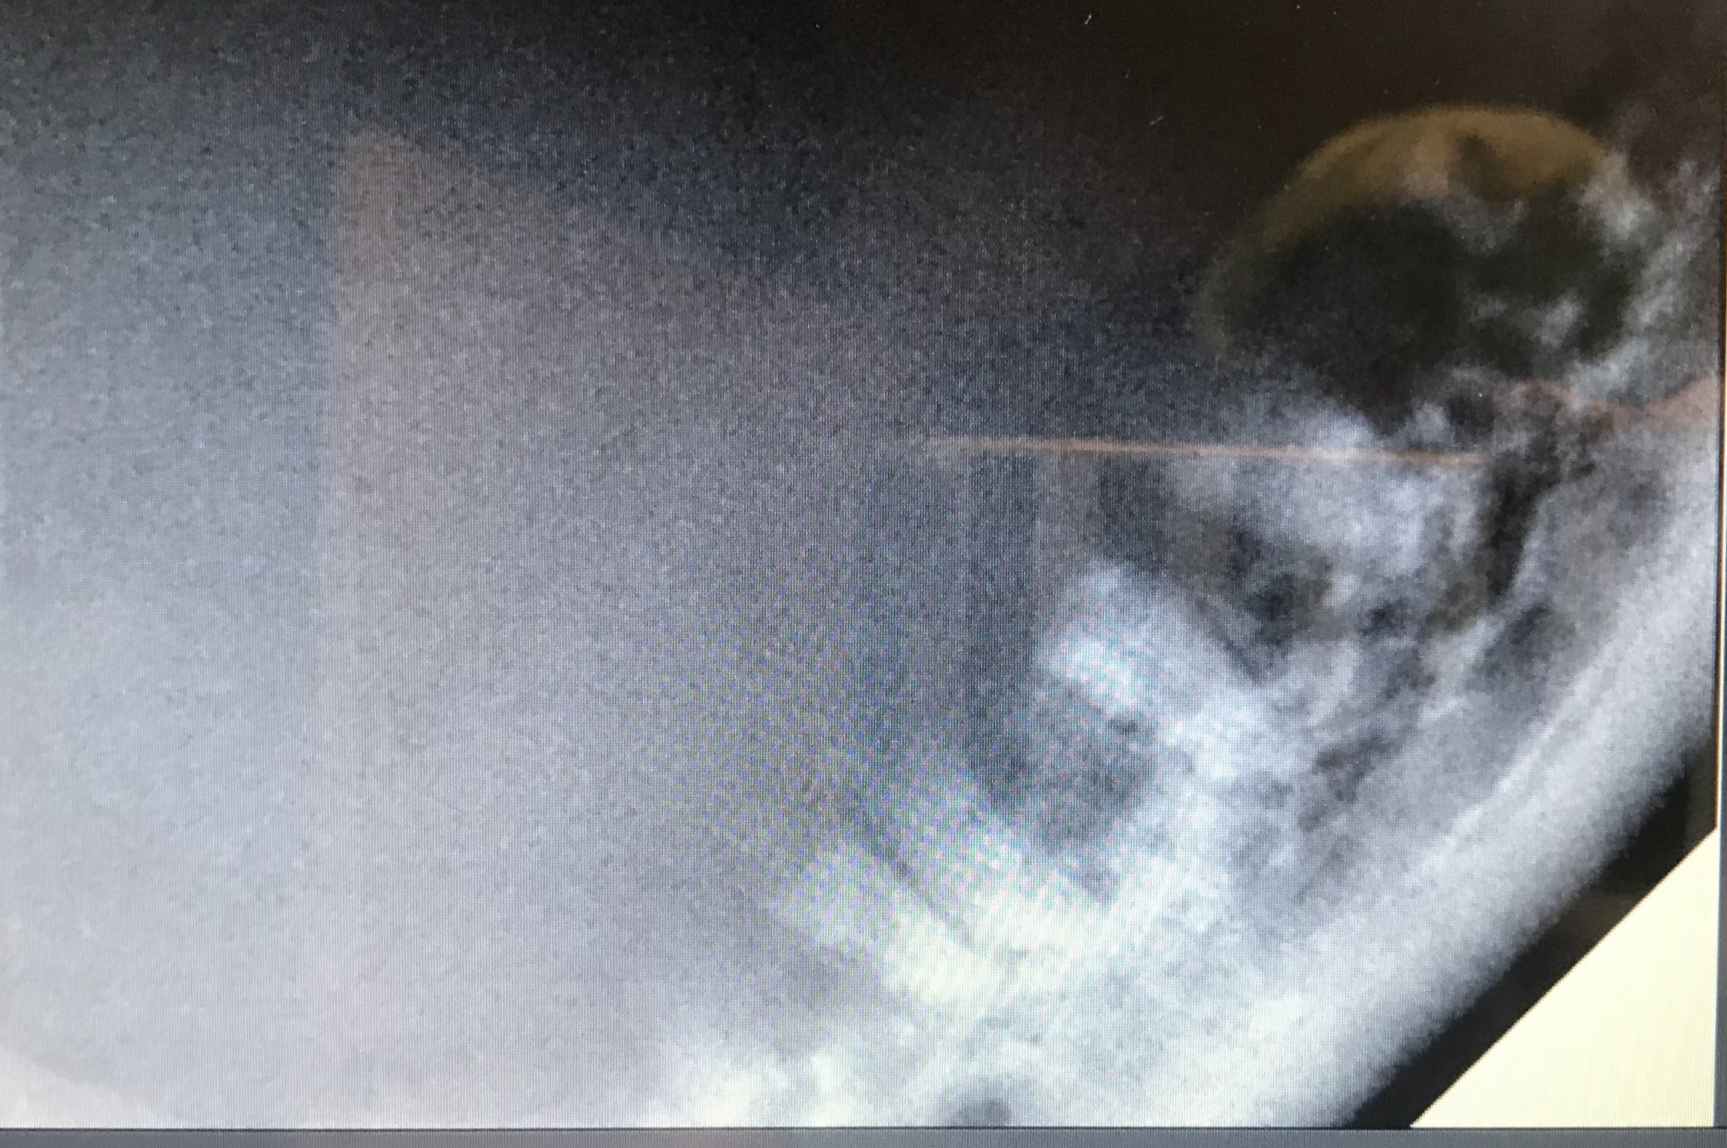

Een hond met ernstige Parodontitis

Op foto 1 en 4

zie je de kiezen in de kaak, ogenschijnlijk nog mooie elementen om te zien, maar

Op foto 2 en 5

zie je de röntgenfoto's van deze kiezen. Opvallend is de grote hoeveelheid verlies van kaakbot rondom eigenlijk alle wortels (verticaal botverlies) en ook het verlies van bot in de splitsing van de wortels (de bifurcatie) en tussen de verschillende kiezen (horizontaal botverlies) Botverlies zie je op een röntgenfoto aan het minder wit zijn van het bot (rond de wortels). Normaal sluit het bot veel hoger aan tegen de wortels en je ziet ook zwarte ruimtes onder de elementen, het bot hoort tot bovenin aan te sluiten.